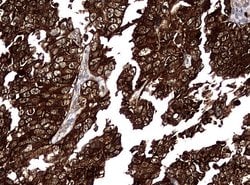

NME1 Mouse anti-Canine, Human, Rat, Clone: UMAB94, liquid, UltraMAB™

NME1 was identified because of its reduced mRNA transcript levels in highly metastatic cells. Nucleoside diphosphate kinase (NDK) exists as a hexamer composed of ′A′ (encoded by this gene) and ′B′ (encoded by NME2) isoforms. Mutations in the gene have been identified in aggressive neuroblastomas. Two transcript variants encoding different isoforms have been found for this gene. Co-transcription of this gene and the neighboring downstream gene (NME2) generates naturally-occurring transcripts (NME1-NME2), which encodes a fusion protein comprised of sequence sharing identity with each individual gene product.Specifications

| Immunocytochemistry, Immunofluorescence, Immunohistochemistry (Paraffin) | |